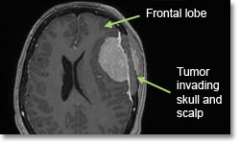

• Magnetic resonance imaging (MRI) scans effectively detect most meningiomas and are best at displaying details of the brain.

• Sometimes a CT scan is obtained to evaluate whether there is any bone (skull) involvement, or if the tumor is calcified.

• If the tumor invades any of the large draining veins, major arteries on the brain surface, or if it is on the underside of the brain, chances of a complete resection decrease and risk of complications increases.